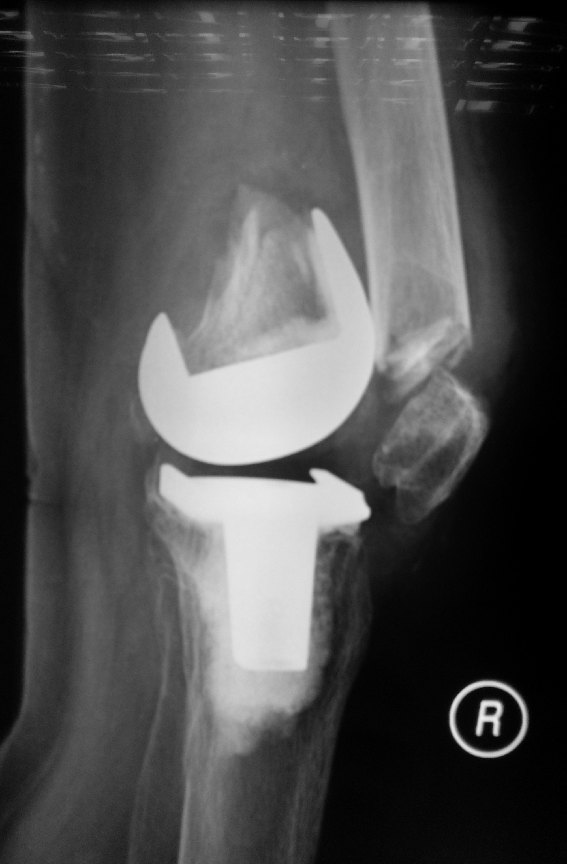

X-rays showed a fracture of the right distal thigh bone (femur) at the position of the previous knee replacement implant.

This patient’s bone was osteoporotic.